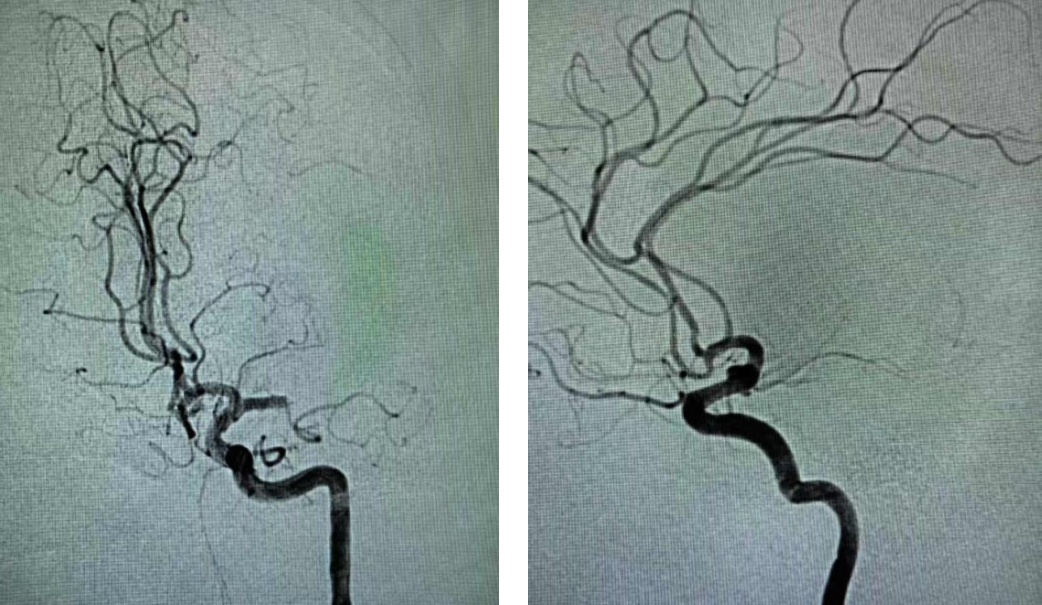

73岁男患,因“右侧肢体无力伴不能言语1小时余”入院;既往有脑梗死病史,未口服脑卒中二级预防药物治疗。入院时心电图提示心房颤动;急诊查颅脑CT排除颅内出血,且左侧大脑中动脉高密度征;急诊查头颈部CTA提示左侧大脑中动脉M1段闭塞,急诊查头颅CTP提示左侧大脑半球低灌注。考虑心源性脑栓塞,急诊行静脉溶栓桥接机械取栓治疗,最终病人恢复正常出院。

术前DSA

术后DSA